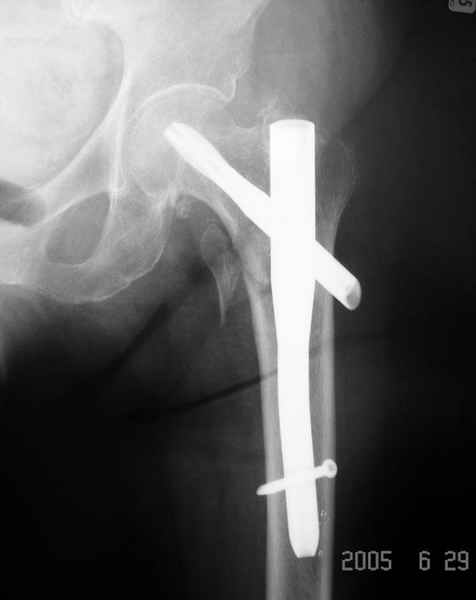

Дорогие коллеги,Как правильно определить такой перелом по классификации AO?

Как два отдельных или есть один соответствующий код? Фиксировать-то оба можно одним фиксатором...

Как раз недавно у меня был примерный случай: больному 36 лет, поступил ночью, травма в результате мотоциклетной аварии, кроме чрезвертельного и спирального перелома левого бедра имеется переломы костей предплечья с этой же стороны. Скелетное вытяжение, а на следующий день больной про оперирован на ортопедическом столе с дистракцией. Чтобы не расколоть чрезвертельный перелом провели временную спицу ближе к переднему кортексу, из малого разреза костодержатель для репозиции, а фиксацию провели антиградным штифтом. Этапы операции на снимках.

Реконструкционный гвоздь.

Да, сейчас это и у нас самый напрашивающийся выбор. Сделали гвоздем ChM, картинки в приложении.